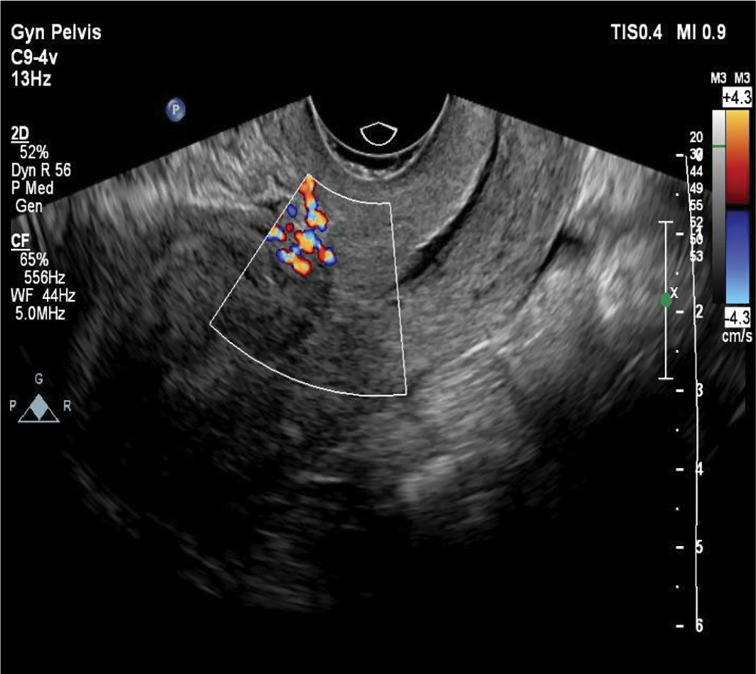

子宫动静脉畸形(AVM)是一种罕见但可能危及生命的疾病,其特征是阴道出血。诊断可以通过各种成像方式建立,包括多普勒超声,磁共振成像(MRI),计算机断层扫描(CT),或盆腔血管造影。治疗的选择受几个因素的影响,包括患者的年龄、临床症状、生育愿望、畸形的大小和解剖位置。对于育龄期希望保留生育能力的有症状的AVM患者,子宫动脉栓塞(UAE)被认为是首选的治疗方法。本文是关于子宫动脉栓塞失败后难治性阴道出血的处理。本报告提出一个病例子宫AVM在一个32岁的女性谁经历了异常阴道出血后人工流产。经多普勒超声证实子宫AVM的诊断。虽然进行了双侧UAE,但患者仍有明显的阴道出血。栓塞手术失败后,通过双侧腹下动脉结扎对患者进行了有效的治疗。阴道异常出血可能提示子宫动静脉畸形,特别是有剖宫产、人工流产或宫内扩张刮除(D/C)手术史的患者。虽然经导管UAE通常是一种有效的治疗方法,但它可能不是在所有情况下都成功。

Uterine arteriovenous malformation (AVM) is an uncommon yet potentially life-threatening condition characterized by significant vaginal hemorrhage. Diagnosis can be established through various imaging modalities, including doppler ultrasound, magnetic resonance imaging (MRI), computed tomography (CT), or pelvic angiography. The choice of treatment is influenced by several factors, including the patient's age, clinical symptoms, reproductive aspirations, and the size and anatomical location of the malformation. For symptomatic AVM in patients of reproductive age who wish to preserve fertility, uterine artery embolization (UAE) is considered the preferred therapeutic approach. This article is about the management of resistant vaginal bleeding after unsuccessful uterine artery embolization. This report presents a case of uterine AVM in a 32-year-old female who experienced abnormal vaginal bleeding following an induced abortion. The diagnosis of uterine AVM was confirmed via doppler ultrasonography. Although bilateral UAE was performed, the patient continued to experience significant vaginal bleeding. Following the unsuccessful embolization procedure, the patient was effectively managed through bilateral hypogastric artery ligation. Abnormal vaginal bleeding may be indicative of uterine AVM, particularly in individuals with a history of cesarean delivery, induced abortion, or dilation and curettage (D/C) procedures. While transcatheter UAE is generally an effective treatment, it may not succeed in all cases.